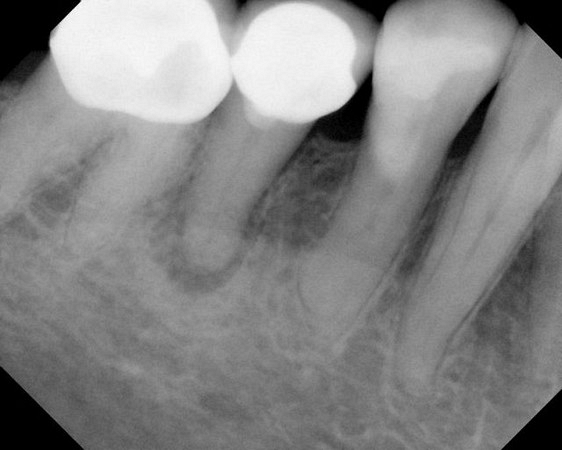

A root canal or filling is a sequence of treatments ( 1-2 appointments) resulting in the elimination of infection and protection of the decontaminated tooth from future bacterial invasion. The inflamed or infected tooth pulp (made of nerve tissue, blood vessels and other cellular entities) is removed, cleaned and disinfected, then filled and sealed with gutta-percha, a rubber-like inert filling material.

See xrays of before and after a root canal is completed below